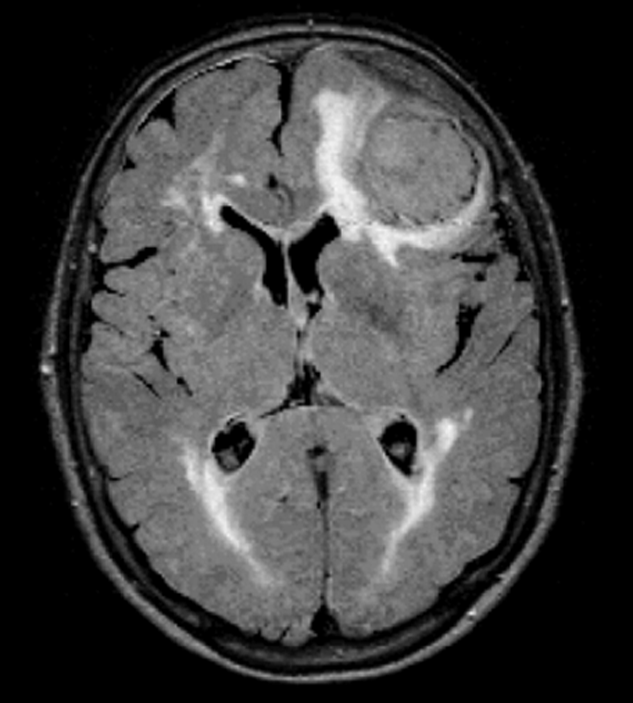

Figura 10-11:

FLAIR. TR = 8000 ms, TE = 120 ms, TI = 2000 ms. The brain lesions caused by the pressure of huge me­nin­gi­oma are well seen on the FLAIR image.

spaceholder redFLAIR (Fluid Attenuated Inversion Recovery) eliminates the signal from ce­­re­­bro­­spi­­nal fluid by using very long inver­sion times (2000–2500 ms). It is espe­ci­al­ly useful in brain lesions with low contrast (Figure 10-11).

CSF reaches the null point of no signal at an inversion time of ~2000 ms (TR > 8000 ms; TE > 100 ms), depending on field strength  [⇒ De Coene 1992].